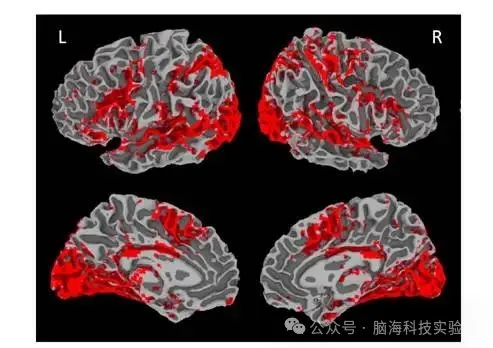

多模态脑影像数据分析平台